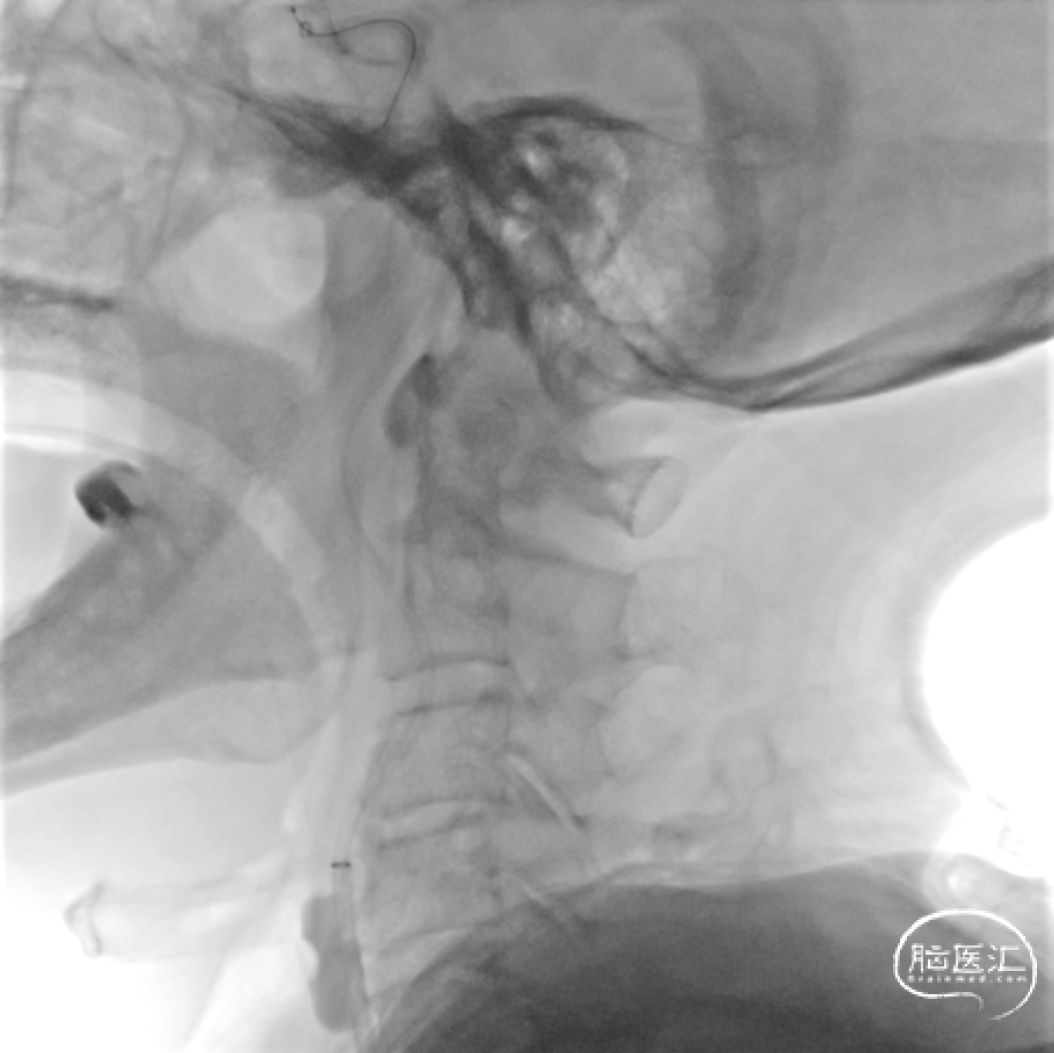

脑血管造影:3型主动脉弓,右侧颈内动脉起始段闭塞,后循环及左侧颈内动脉均未向左侧颈内动脉供血区代偿。

3型主动脉弓,用Mani管超选至右颈总动脉,用260cm加硬泥鳅导丝交换出,在泥鳅导丝导引下,用125cm的多功能管将6F Infinity长鞘置于右颈总动脉,提供稳定支撑。

在Synchro2微导丝及微导管引导下,Catalyst7抽吸导管顺利到达颈内动脉末端。

Catalyst 7抽出大量负荷血栓,大脑中动脉上干仍未显影。

微导丝微导管超选至大脑中动脉上干,微导管造影确认在血管内真腔内,释放Solitaire 4×20mm。

Solitaire 4×20mm支架锚定Catalyst 7抽吸导管到达M1段,抽吸导管负压,拉出取栓支架,取栓过程中Catalyst 7维持稳定。

两次支架取栓取栓取出血栓,血管再通。